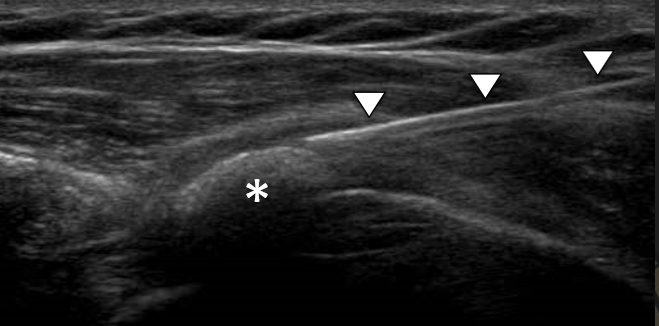

V kolikor so kalcinati večji od 8mm in so enakomerne strukture lahko pod ultrazvočno kontrolo opravimo tudi punkcijo kalcinata in kalcinat izperemo. Poseg se opravi v lokalni anesteziji in traja približno 30 minut. Bolečina lahko traja tudi nekaj dni po posegu. V teh primerih svetujemo jemanje analgetikov. Nekaj dni po posegu priporočamo postopno stopnjevanje aktivnosti, izvajanje vaj, plavanja, nordijske hoje in fizikalne terapije in po 2 -3 mesecih vrnitev željenim aktivnostim.